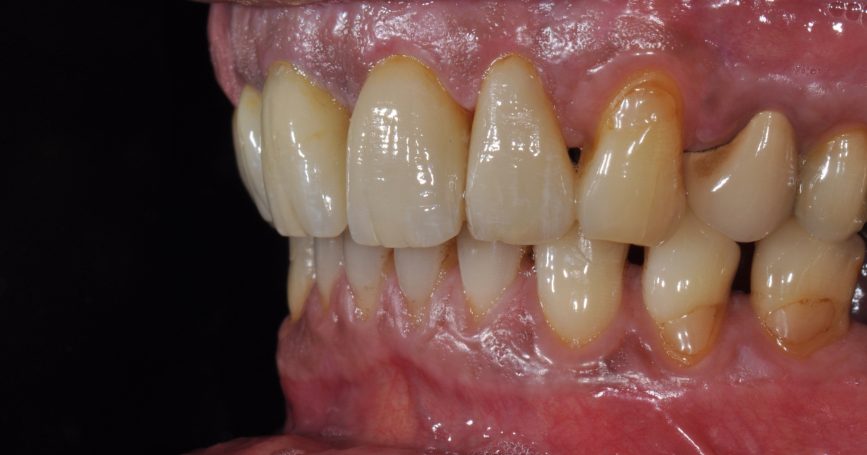

Teleskopierende Oberkieferbrücke mit Vorher- und Nachher-Situation des Patienten.

Teleskopierende Oberkieferbrücke. Wie die eigenen Zähne, aber einfach zu reinigen.